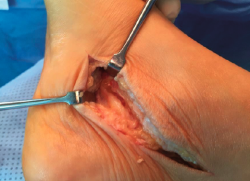

Con el diagnóstico de síndrome del canal del tarso posterior, secundario a una lesión quística ocupante de espacio, se indicó el tratamiento quirúrgico de dicha lesión, procediendo a la liberación del nervio tibial posterior, mediante apertura del retináculo flexor y de la fascia del abductor del hallux, exéresis del ganglión y exoneurolisis de sus ramas plantar medial y lateral (Figura 3).

Figura 3. Imagen intraoperatoria del canal tarsiano. Se observa el ganglión en su interior.